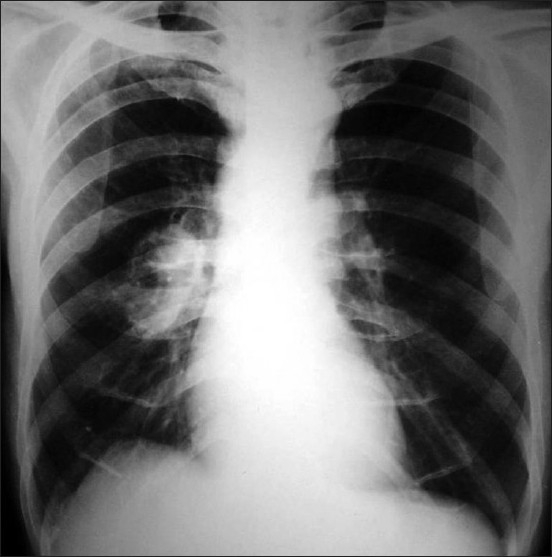

A 55-year-old man comes to the emergency department because of 1 month of left flank pain that radiates to the groin and intermittent productive cough for 4 months. He has smoked cigarettes since age 20. Urinalysis shows hematuria. X-ray of the chest is shown. Serum angiotensin-converting enzyme level is normal.

Copyright © Lung India

Which of the following abnormalities most likely led to this patient’s hematuria?

A. High vitamin D levels

B. Hypercalciuria

C. Metastatic cancer to the kidney

D. Metastatic renal cell carcinoma

E. Multiple endocrine neoplasia